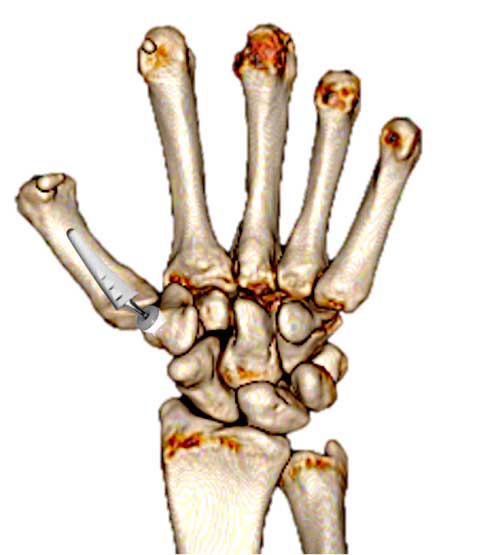

Este sistema de suspensión se llama “MiniThighrope” (Arthrex) y evita que el primer metacarpiano “caiga” en el espacio que ha dejado el trapecio. El cual se rellenará de tejido cicatricial y coágulos y actuará como un sistema de amortiguación evitando el roce entre dos huesos y, por tanto, el dolor.

Extirpación del trapecio y colocación entre primer y segundo metacarpiano. Tratamiento 1

colocación de un espaciador entre primer y segundo metacarpiano tras extirpación del trapecio. Trataamiento 2